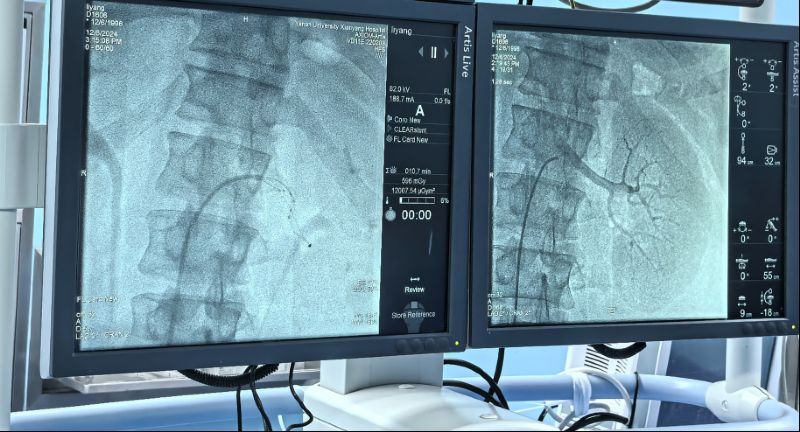

术中通过对左右肾动脉造影,了解肾动脉解剖结构、评估肾脏灌注情况。而后顺利将射频消融导管的电极头推至肾动脉主干及分支中远段,双侧肾动脉累计消融16次,涵盖相应分支及主干,共完成78个有效消融点,完成后再次行双肾动脉造影,评价手术对肾动脉形态和肾血流影响,累计用时仅60分钟高效圆满完成。术前血压由154/110mmHg,手术完成后血压130/94mmHg,即刻血压下降效应明显,直至目前术后减少三种降压药物,监测血压维持在120/70mmHg左右,手术效果理想,长期血压下降情况我们将持续随访关注。